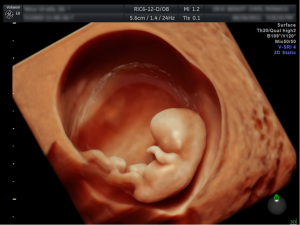

Es el método más seguro para evaluar el estado general del embarazo, cuando la gestación no supera las 13 semanas, se debe realizar por vía vaginal para poder valorar mejor.

Se introduce el transductor cubierto con un condón por la vagina y se evalúa:

- Tamaño del saco gestacional.

- Presencia de embrión.

- Si hay embarazo múltiple.

- Vitalidad del embrión.

- Distancia entre el saco gestacional y el orificio del cuello uterino.

- Si hay hematomas.

- Descartar embarazos ectópicos.

- Se calcula tiempo de gestación.